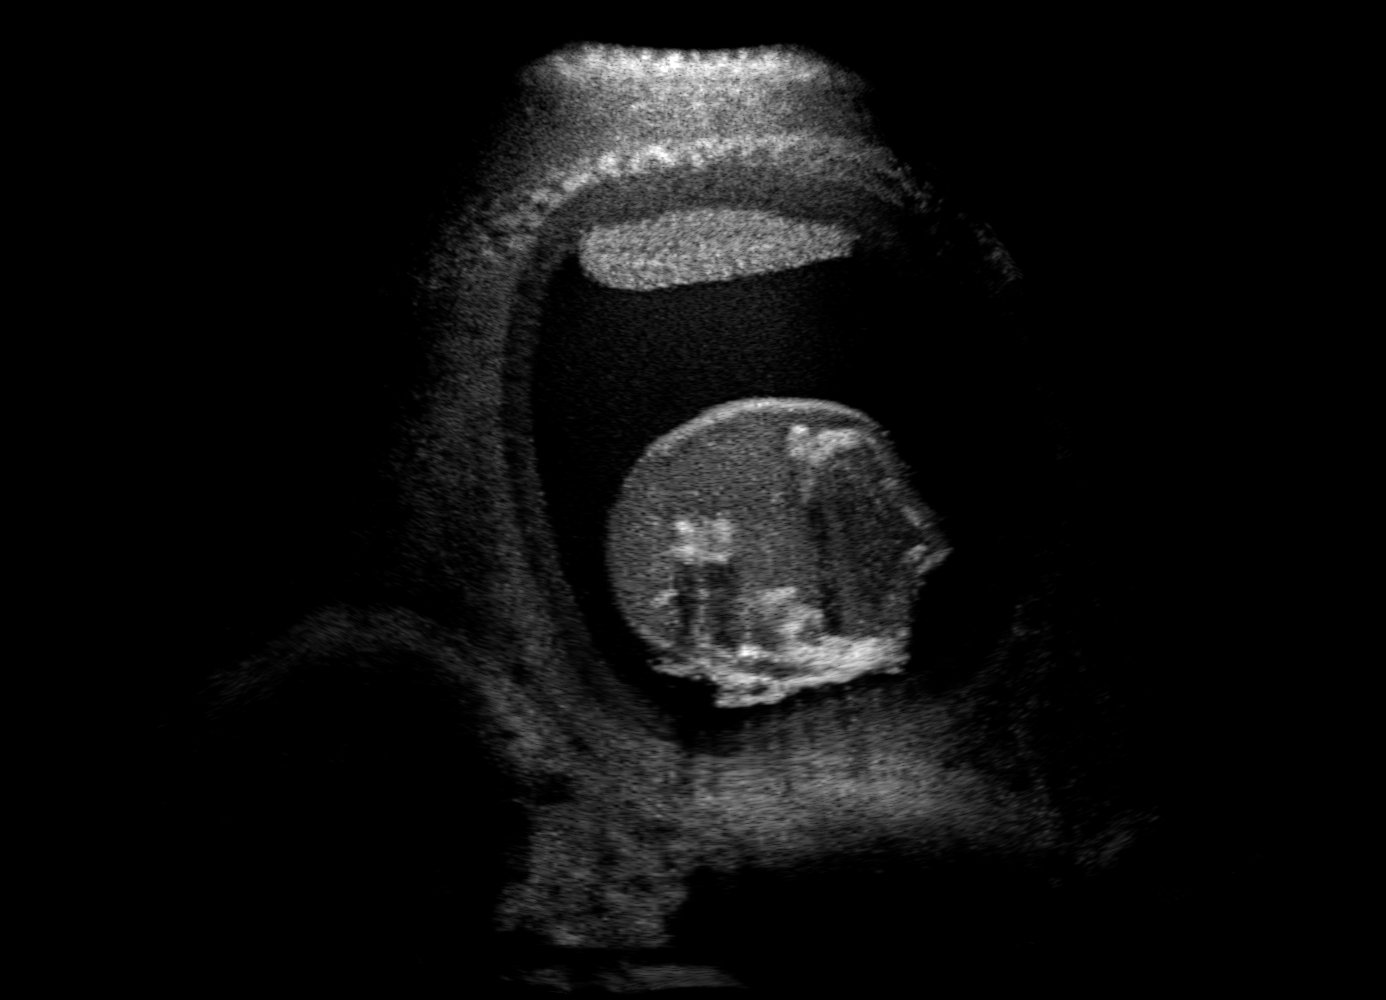

Qualitative evaluation.

Fig. 2 depicts the qualitative results for all the models mentioned above, with arrows pointing at structures relevant to discussion points below. The visual results of the ablated variants of SA2H show substantial quality degradation compared to the full SA2H model, demonstrating the importance of each proposed architectural contribution. Given only segmentation map in the network input, SA2H-att fails to generate acoustic shadows, e.g. those cast by the ribs. Detailed structures such as the cervical vertebrae are blurred out in the SA2H-concat results, which also contain hallucinated structures mainly due to insufficient preservation of input information along the encoding-decoding path. With SA2H-conv, checkerboard artefacts are observed due to the lack of proposed additional stride-1 convolutional layers. SA2H-noise without any explicit noise input is seen to be sub-optimal at generating textural details. The baseline method NSA2H fails to preserve anatomical structures and acoustic shadows in all cases, while the simulated textures also show significant artefacts such as checkerboard patterns. Realism of different simulation aspects may become relevant given different clinical applications and scenarios. For instance, improved structural preservation, e.g. with the hyperechoic bony structures such as the skull and the ribs, of the final model over its ablated variants and NSA2H may prove relevant in fetal head measurements, while the textural improvements facilitating screening fetal organ maturity, e.g. lungs. Compared to the silver-standard model LSA2H with a low-quality rendered image as additional input, SA2H is seen to be on par in structural preservation. Note that shadowing on homogenous regions (e.g. the rib shadowing on the homogenous lung region on the 4th column of Fig. 2) with our proposed method SA2H is represented more faithfully compared to LSA2H, whereas shadows on structurally complex regions (e.g. the skull shadowing around the heart and surrounding tissues on the 3rd column of Fig. 2) are suboptimal with our SA2H. Therefore, one may have to evaluate our method given particular simulation tasks, e.g. its clinical validity for fetal heart exams. However, even with low quality rendered images, LSA2H leads to artificial enhancements of intensities, lack of acoustic shadows, and low-quality textures especially near the probe, for which SA2H yields satisfactory results as illustrated in Fig. 2.

(a) Target

(b) SA2H

(c) SA2H-att

(d) SA2H-concat

(e) SA2H-conv

(f) SA2H-noise

(g) NSA2H

(h) LSA2H